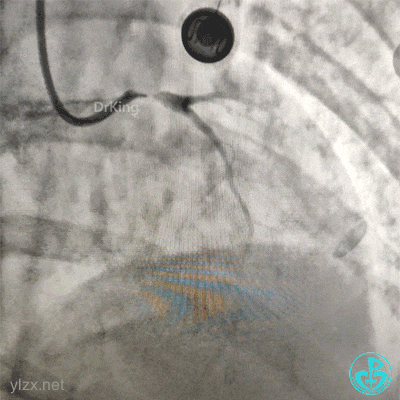

结束手术。

下台时血压127/78mmHg,心率75次/分。